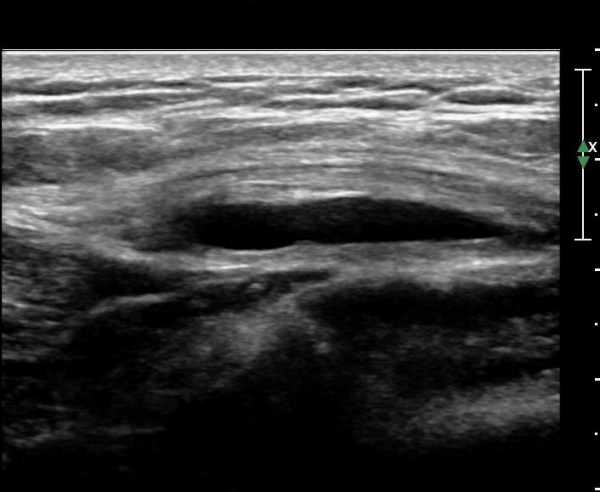

´ëÀüÀÚ ¾ÕÂÊ Á¾´Ü¸é°Ë»ç¿¡¼­ ¼ÒµÐ±ÙÈûÁÙ°ú Àå°æÀÎ´ë »çÀÌ¿¡ ¼ö¾×Àú·ù°¡ ¶Ñ·ÈÈ÷ °üÂûµÈ´Ù(»çÁø 6, 7).